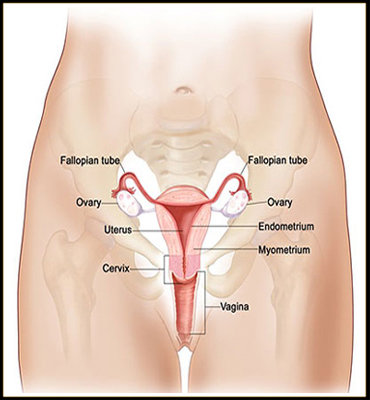

Female Infertility :

- PCOS or PCOD

- Repeated Abortions

- Blocked tube

- Ovarian cyst

- Chocolate cyst

- Endometriosis

- Endometritis

- Uterine Polyp

- Fibroids

- Adenomyosis

Gynaecological

Treat your Menstrual Problems with Ayurveda

- Menopause

- PCOD / PCOS

- Fibroids

- Endometritis

- Polyps

- Adenomyosis

- Vaginal Infections

- Vaginitis

- Candidiasis

- Cervical Erosion

- White Discharge / Leucorrhoea

- Cancers

- Breast Cancer

- Scanty Menstruation

- Painful Menstruation

- DUB – Dysfunctional Uterine Bleeding

- Breast Related Problems